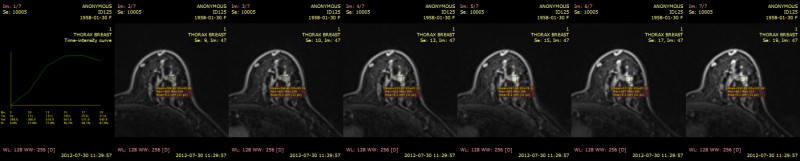

时间-强度曲线(TIC)

时间-强度曲线工具通过绘制注射对比剂后各时间点的信号强度值,可视化病变的强化行为(例如乳腺 MRI 检查)。

5) 从 高级工具 中选择 时间-强度曲线,或使用快捷键 Ctrl + Shift + E。

6) RadiAnt DICOM Viewer 将自动选择用于生成曲线的序列。如需使用其他序列,可手动修改选择。点击 确定 确认选择并生成曲线。

7) 将添加一个新面板,其中包含时间-强度曲线以及用于计算的各动态序列中感兴趣区域的截图。

8) 双击面板将其最大化,可查看详细的曲线图。